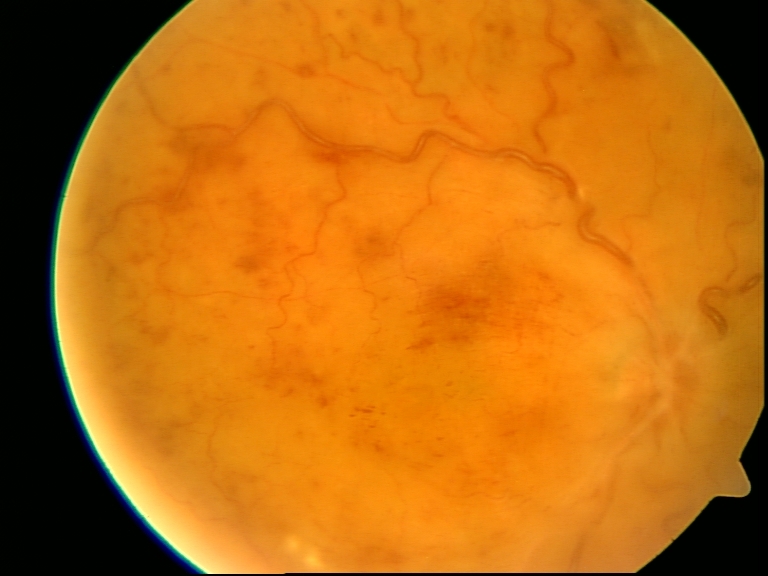

Retinale Venenverschlüsse

Retinopathie ist der Fachbegriff für Netzhauterkrankungen des Auges. Diese Netzhauterkrankungen werden durch Gefäßerkrankungen, wie retinale Venenverschlüsse oder diabetische Retinopathien hervorgerufen.

Retinale Venenverschlüsse führen zur Unterversorgung der Sehzellen und ihres Stoffwechsels. Das führt zu Versorgungsengpässen, die die Sehkraft gefährden können.

Bei der diabetischen Retinopathie können ebenfalls Venenverschlüsse sowie Veränderungen an den Gefäßwänden auftreten. Diese werden porös und bekommen Löcher, durch die Blut austritt und in den Glaskörper einblutet, was das Sehvermögen ebenfalls stark gefährdet.

- Zentraler Venenverschluss (ZVV): tritt im Ein- und Ausgangsbereich des Sehnervs („blinder Fleck“) auf und führt zur starken Verschlechterung der Sehleistung

- Venenastverschluss (VAV): tritt am häufigsten dort auf, wo Venen und Arterien sich kreuzen

Venenastverschlüsse treten zwar öfter als Zentralvenenverschlüsse auf, führen aber verglichen damit zu weniger starken Verschlechterungen der Sehleistung.

Des Weiteren entwickelt sich bei vielen Patienten aus dem Venenastverschluss oder dem Zentralvenenverschluss ein Makulaödem. Darunter versteht man Netzhautverdickungen und Flüssigkeitsansammlungen an der Makula. Die Makula ist der Bereich des schärfsten Sehens.